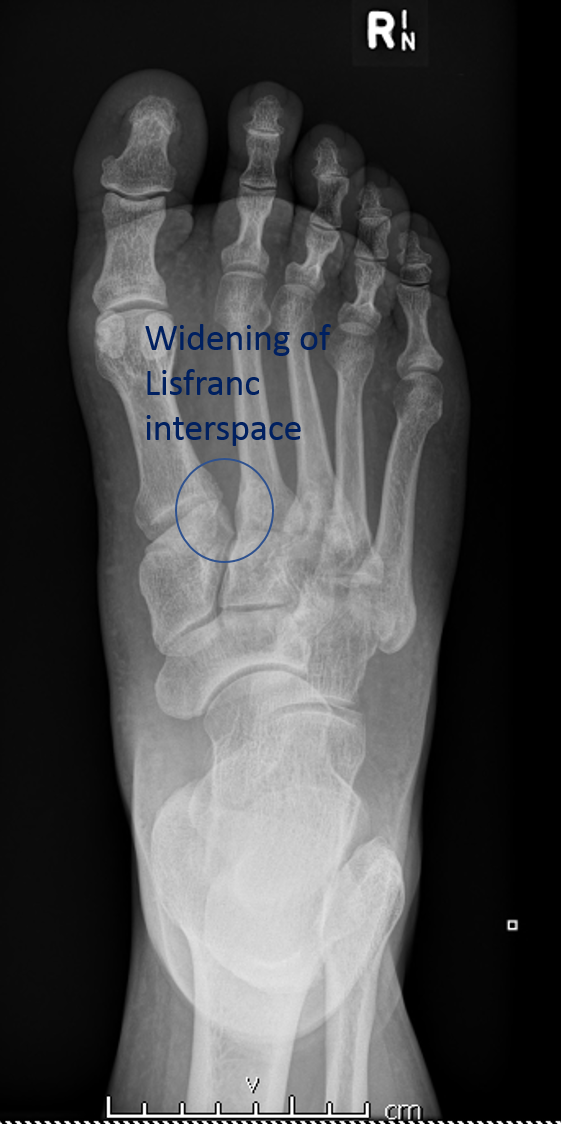

lisfranc损伤是常见的跗跖关节骨折和/脱位。

CASE 2 M40 足伤

骨折和LISFRANC间隙增宽的注解图像